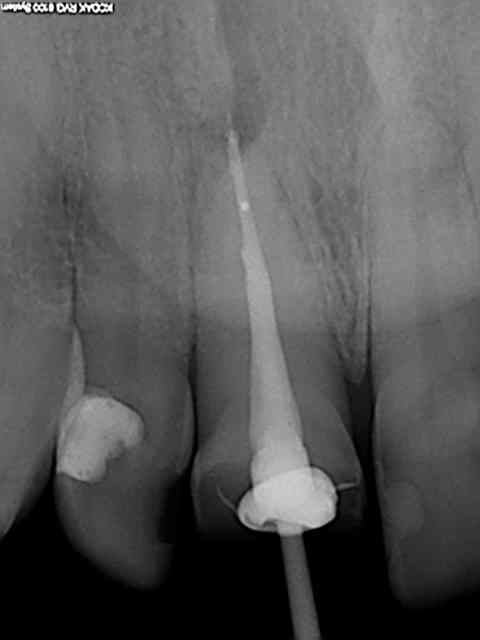

R29 uvltlt - Eugenol

R49 enunsh - Eugenol

R22 vkd0tr - Eugenol

R23 pmkimv - Eugenol

R26 gr1kkt - Eugenol

R34 w9wpow - Eugenol

Img 0052 dkvbyu - Eugenol

Leandro

28/02/2013 à 21h54

Joli travail!